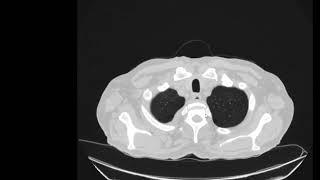

Рак позвоночника – злокачественная опухоль, которая развивается в позвоночнике. Это редкое заболевание и, как правило, оно является вторичным раком, возникающим из метастазов других раковых опухолей, распространяющихся на позвоночник.

Метастазы рака позвоночника.